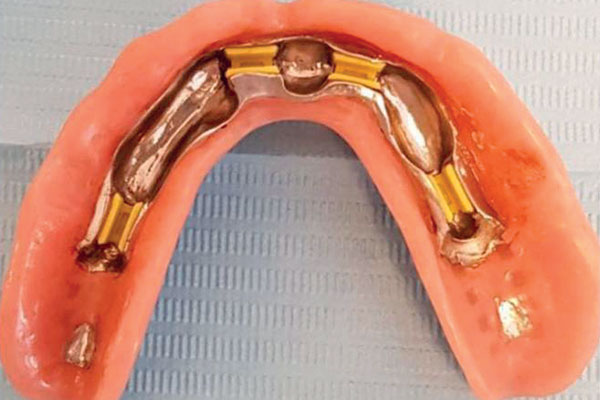

È una protesi completamente rimovibile e personalizzata, la cui stabilità è garantita dal posizionamento sull’arcata da riabilitare di due o quattro impianti collegati tra loro eventualmente da una barra. La protesi risulterà stabile perché agganciata proprio agli impianti o alla barra con attacchi particolari.